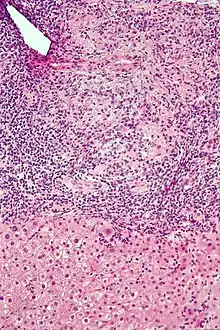

Histology of primary biliary cholangitis × 200 liver biopsy

On microscopic examination of liver biopsy specimens, PBC is characterized by chronic, non-suppurative inflammation, which surrounds and destroys interlobular and septal bile ducts. These histopathologic findings in primary biliary cholangitis include the following:[34]

- Inflammation of the bile ducts, characterized by intraepithelial lymphocytes, and

- Periductal epithelioid granulomata.

- Proliferation of bile ductules

- Fibrosis (scarring)

The Ludwig and Scheuer scoring systems have historically been used to stratify four (1–4) ‘stages’ of PBC, with stage 4 indicating the presence of cirrhosis. In the new system of Nakanuma, the stage of disease is based on fibrosis, bile duct loss and features of cholate-stasis, i.e. deposition of orcein-positive granules, whereas the grade of necroinflammatory activity is based on cholangitis and interface hepatitis. The accumulation of orcein-positive granules occurs evenly across the PBC liver, which means that staging using the Nakanuma system is more reliable regarding sampling variability.